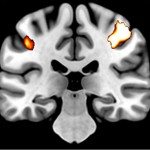

• Neuroimaging